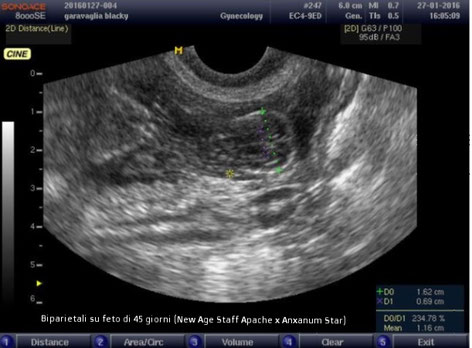

- Al 21° giorno dall'accoppiamento effettuiamo la prima ecografia per verificare la gravidanza in corso e la corretta maturazione degli impianti nei quali, successivamente, sarà ben visibile il feto. Questo primo controllo ecografico è molto utile per stabilire che non ci sia un riassorbimento fetale in corso;

- Al 40° giorno dall'accoppiamento effettuiamo il secondo controllo ecografico per verificare la salute dei feti, il flusso cardiaco e le biometrie per stabilire la data del parto con una precisione di +1/-1 giorno;